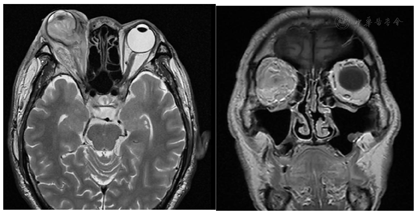

病例1,患者,男性,65岁,汉族,2022年3月以"右眼突出,巩膜并眼睑红肿伴视力下降8 d"为主诉入院。患者于2022年3月22日晨起后自觉右眼分泌物较前增多,伴巩膜红肿并视力下降,可视物。自行使用"红霉素眼膏"效果欠佳;自觉眼压增高,眼球突出,视力进行性下降,视物不能,无光感。就诊当地医院眼眶CT:(1)右侧眼球突出、形态及密度异常,右侧眼球后方间隙模糊;(2)右侧内、外直肌略增粗;眼眶MRI:右侧眼球形态及信号异常、右侧眼球后方脂肪间隙信号异常,右侧内外直肌略增粗且信号略增高。2022年4月1日转入新疆医科大学第一附属医院诊断为"脓毒血症,右眼眼球炎,右侧眼部蜂窝组织炎,低钾血症,甲状腺术后",患者右眼球脓肿伴高度凸出(图1)全身多发感染,眼科无法行局部手术治疗,为明确感染类型及筛查全身感染情况收治新疆医科大学第一附属医院感染病肝病中心进一步治疗。既往史:无特殊。家族史:无特殊。

病例1,入院体格检查:体温36.9℃,脉搏110次/min,呼吸26次/min,血压109/88 mmHg(1 mmHg=0.133 kPa),体质量55 kg。神志清楚,精神好。体格检查:左眼未见明显异常;右眼:眼球突出,眼睑红肿明显,内眦上方可见皮肤破溃,表面有血痂,结膜充血,结膜囊内可见大量黄色脓性分泌物及血性分泌物,角膜表面干燥、毛糙,余结构视不入。压痛(-);眼球运动:右眼不能转动,左眼各方向运动未见明显异常。余心肺腹体格检查无特殊。实验室检查:乙肝、丙肝、HIV阴性;痰结核菌涂片阴性,尿常规、甲状腺功能5项、真菌D-葡聚糖检测、梅毒螺旋体血清学、巨细胞病毒DNA测定、呼吸道病原体9项、甲型流感病毒抗原阴性。结核感染T淋巴细胞:阴性。结缔组织疾病阴性。血培养、前列腺脓液培养、眼周分泌物培养:肺炎克雷伯菌(全敏感)。2022年4月2日(术前):右侧眼球3度突出;右侧球后脂肪间隙及右侧眶周软组织所见,考虑炎性假瘤;右侧眼球变形并内密度不均匀增高;鼻中隔偏曲;双侧上颌窦炎并左侧上颌窦囊肿;右侧下鼻甲肥大。2022年4月6日肾输尿管膀胱前列腺,双肾未见明显异常。双侧输尿管未见扩张。膀胱未见明显异常。前列腺增大(考虑:前列腺增生,其他待排)并其内回声不均,建议结合PSA检查。盆腔内低回声区(与前列腺分界不清),结合病史考虑:感染性病灶可能性大,6.3 cm×4.4 cm的低回声(图2)。2022年5月6日(术后)双肺轻度间质性改变,双肺散在炎症,肝右叶低密度,感染性病变可能性大(1.44 cm)前列腺增生,前列腺内低密度灶,考虑感染性病变,脓肿可能。右侧颞叶皮层,左侧小脑半球及左侧放射冠区异常强化结节,考虑脓肿较前水肿范围缩小,结节强化范围及幅度略缩小,请结合临床水肿,右眼球摘除术后改变(图3)。